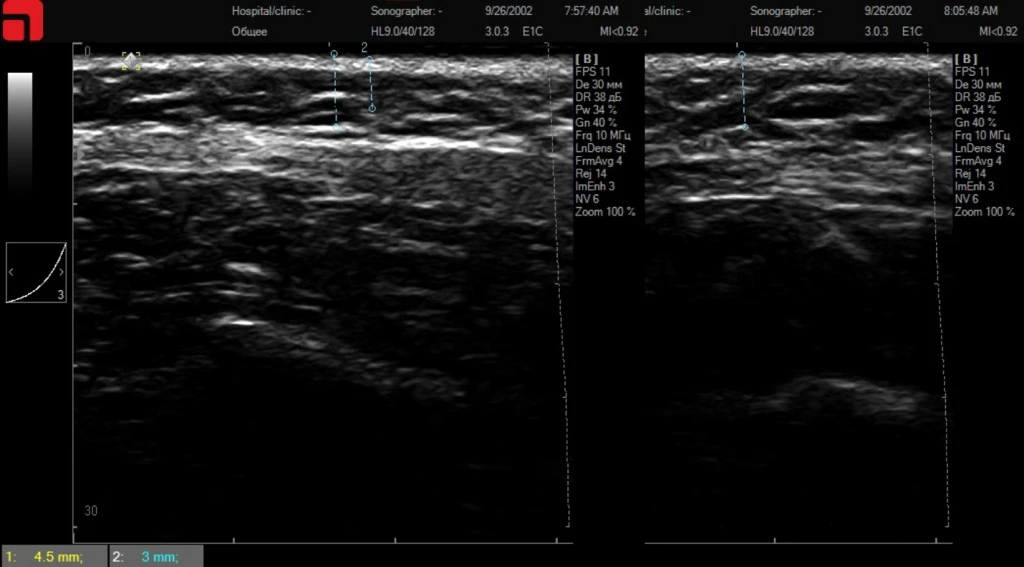

Рис. 5. На сканограмме отмечаются слабовыраженные трабекулы и септы подкожно-жировой клетчатки – меньше «мишеней» для HIFU SMAS-лифтинга.

В клинической практике часто встречаются пациенты с субклиническими формами дисплазии соединительной ткани и сопутствующим данному состоянию снижением количества соединительной ткани в подкожно-жировой клетчатке и на SMAS.

Проведение ультразвуковой диагностики высокого разрешения позволяет выявлять таких пациентов и подходить к ним с комплексным лечением для получения оптимальных результатов. Можно использовать комбинированный протокол – коллагенстимулирующие процедуры с последующим аппаратным SMAS-лифтингом Doublo.

Рис. 6. Сканограмма до процедуры коллагенстимуляции, отмечается резко сниженное количество соединительной ткани в подкожно-жировой клетчатке и на SMAS.

Рис. 7. Сканограммы через 6 месяцев после процедуры коллагенстимуляции. Отмечается уплотнение кожи, соединительной ткани в подкожно-жировой клетчатке.